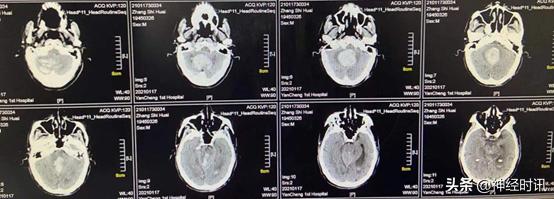

入院时急诊头颅CT检查提示小脑大量出血,量约30 ml,且破入脑室,脑干已受压,随时可能出现呼吸骤停,建议急诊手术清除小脑血肿,病情及手术相关风险向患者家属详细交代,其家属经过协商后拒绝手术,要求对症保守治疗。

入院时(1月18日),急诊头颅CT提示小脑出血约30 ml